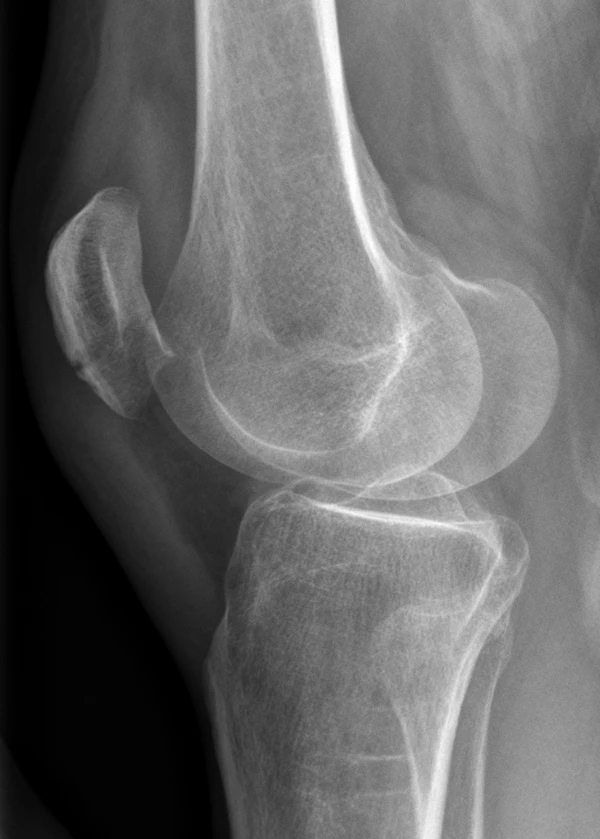

- Рентгенография коленного сустава двух проекциях

Известно множество классификаций переломов надколенника. Классификация переломов разнообразна и основана характере перелома и степени смещения его отломков. Переломы делятся на: без смещения (диастаз до 2—3 мм) и со смещением (диастаз более 3 мм или при неконгруэнтности суставной поверхности более 2 мм). Морфологически разделяют на поперечные, продольные, звёздчатые (оскольчатые) и отрывные переломы верхнего и нижнего полюсов. Также выделяют многофрагментные и остеохондральные переломы. Кроме того, выделяют открытые и закрытые переломы[3].

- Двудольный надколенник[2]